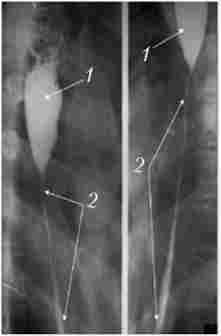

Після опікові стриктури зазвичай циркулярні - трубчасті або кільцеподібні, рідше мембранозний, клапанні. Просвіт органу в області стриктури різко звужений аж до повної облітерації, при цьому визначається супрастеіотічне розширення у вигляді конуса або чаші (рис. 9.6).

Контури звуження бувають досить гладкими, рельєф слизової відсутня, перистальтика зазвичай не виявляється.

Рентгенограма стравоходу при його післяопіковому рубцовом звуженні

Мал. 9.6. Рентгенограма стравоходу при його післяопіковому рубцовом звуженні: